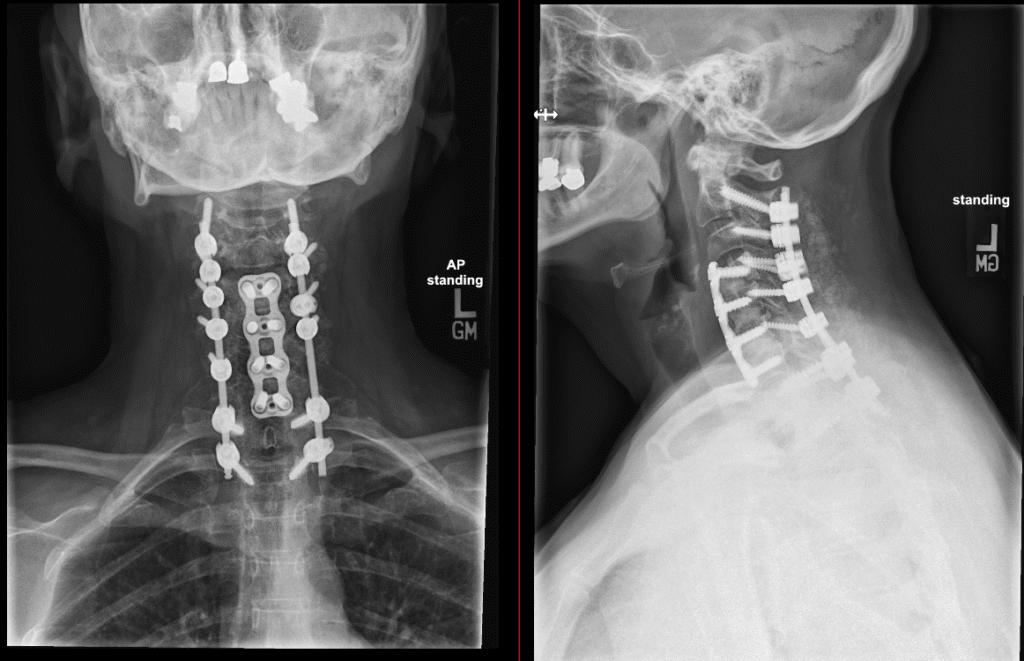

Posterior Cervical Spine Surgeries

Posterior Cervical Fusion